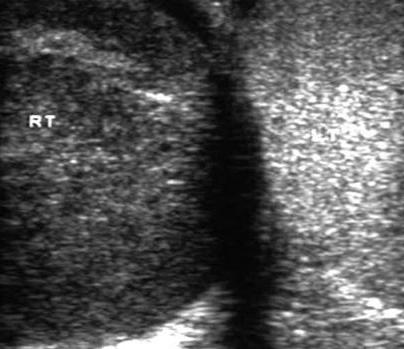

A 37-year-old male patient presents to the emergency department with a 3-month history of a gradual increase in the size of his right testis. He denies any pain or trauma. He has no dysuria or frequency. Physical exam reveals an enlarged, painless, firm right testis. The patient was sent for an ultrasound, which reveals a hypoechoic mass with concern for malignancy, which resulted in an urgent urologic referral. Primary testicular tumors are the most common solid organ malignant tumor in men between what ages? A. 5-20 B. 20-35 C. 35-50 D. 50-65